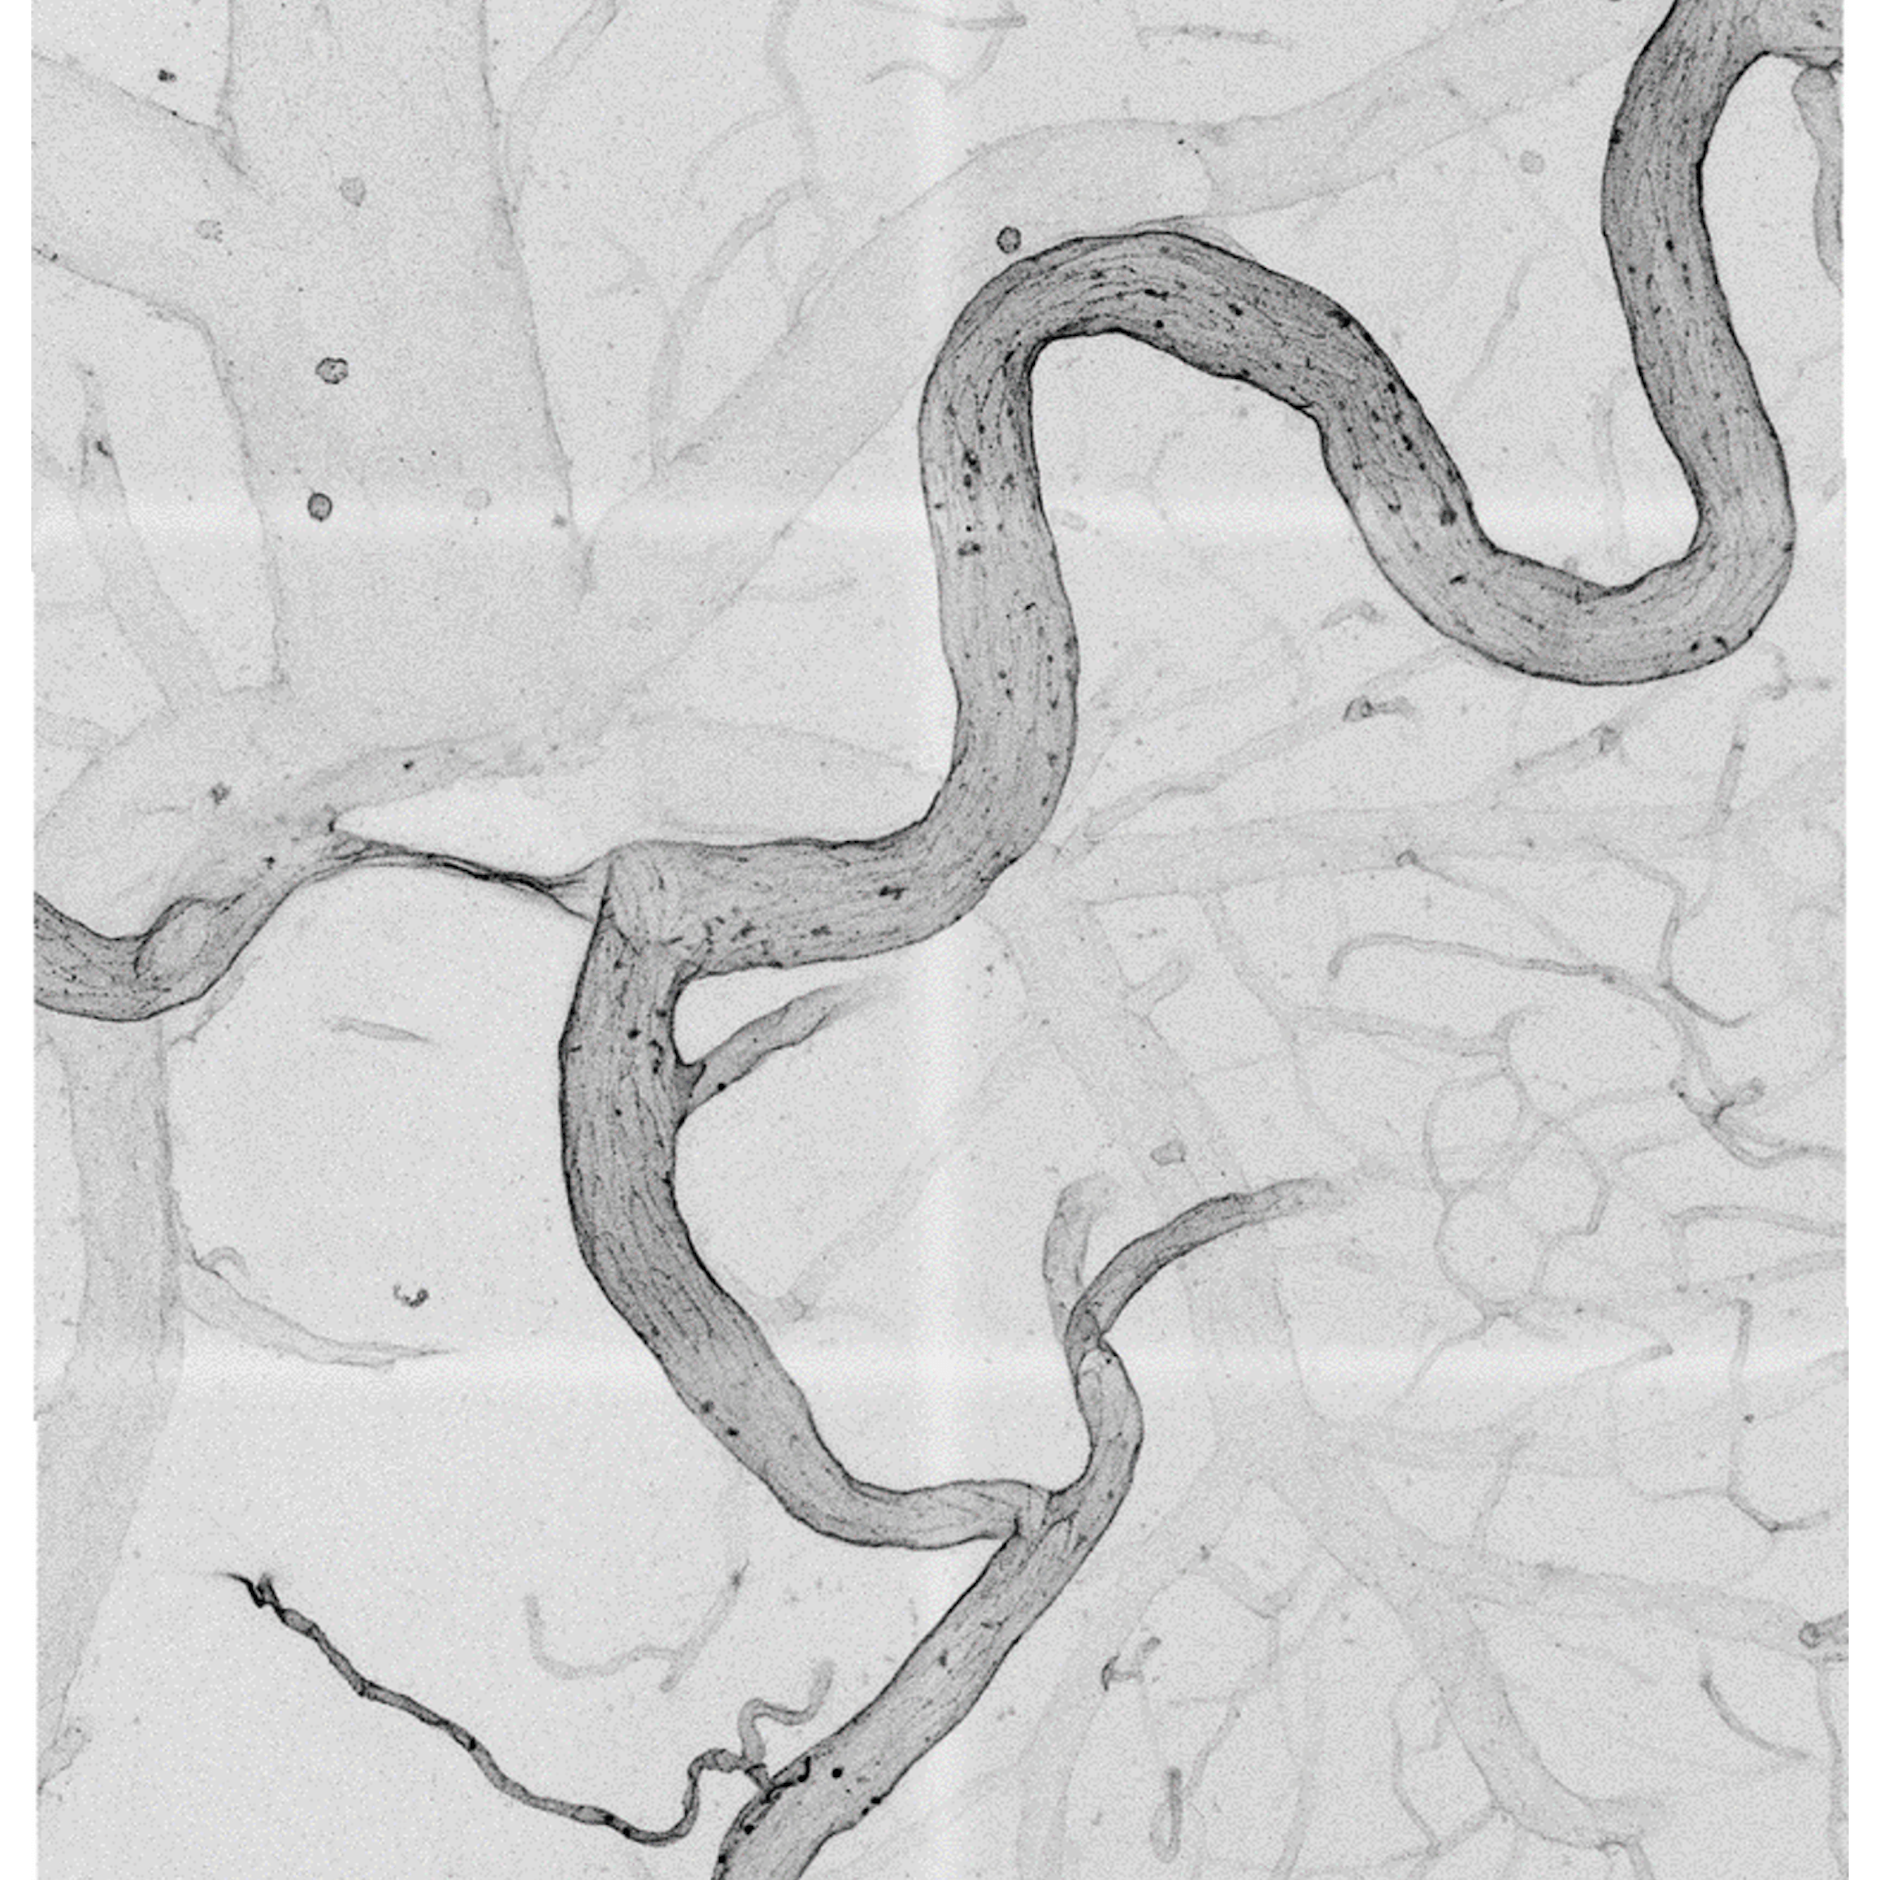

Sie entdeckten vor etwa zwei Jahrzehnten die sogenannte Aussprossung der Blutgefäße. Bildlich gesehen handelt es sich um lange, fadenförmige Auswüchse von Leitzellen, die nachfolgenden Zellen die Richtung weisen. Daraus bauen sich feine Kapillaren auf, die sich zu einem Netz verbinden. Sind solche Vorgänge wichtig, um Krankheiten zu verstehen, die mit den Blutgefäßen zusammenhängen?

Ja, der Grundansatz ist, dass wir erst einmal verstehen wollen, wie die einzelnen Zellen zusammenarbeiten, um das geordnete Muster zu bilden. Verantwortlich für die neue Aussprossung von Blutgefäßen sind die sogenannten Endothelzellen, die die innere Auskleidung aller Gefäße bilden. Sie weisen den neuen Gefäßen den Weg. Erst dann werden die unterstützenden Glattmuskelzellen rekrutiert, um die Gefäße zu verstärken. Endothelzellen sind so wichtig, weil sie ähnlich wie Nervenzellen sehr langlebig sind. Was wir an Schädigungen über Jahrzehnte dort mitnehmen, das bleibt auch. Und das bestimmt vermutlich auch, wie zukünftige Krankheitsverläufe ablaufen.